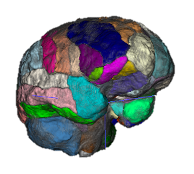

Quantitative Volumetry

Measuring the volume and appearance of brain and spinal cord structures can yield important insights about the health of the underlying tissue. Abnormal shrinkage of certain brain areas early in the course of multiple sclerosis (MS) can herald clinical decline. For example, the thalamus is one of the earliest structures to shrink in MS and we collaborate with the Saranathan Lab in assessing thalamic subnuclear segmentation. We employ a wide variety of tools to accurately quantify brain structures. Among many, these can include Freesurfer, FSL, SPM, C3D, ITK-SNAP, 3D Slicer, and ANTs. We are now implementing newer deep learning segmentation tools that can be trained on relatively small datasets as well. The Principal Investigator (PI) runs a longitudinal, observational study of MS (the OPTIMUM study) to study real-world information from persons with MS, a resource that allows new insights into the disease by combining MRI with clinical data informatics.